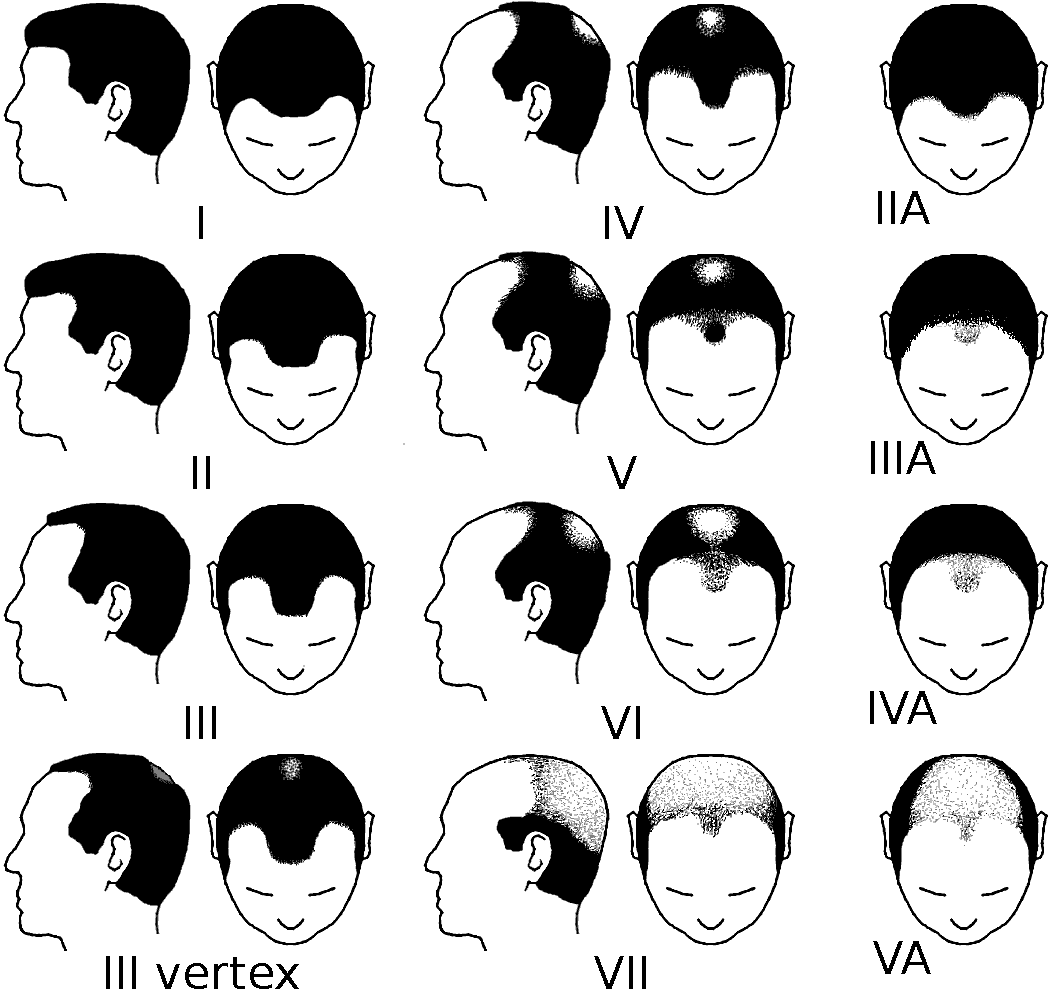

La scala Hamilton-Norwood classifica le fasi della calvizie (Wikimedia)

La perdita di capelli è un processo naturale che si verifica con l’avanzare dell’età. Non riguarda tutte le persone allo stesso modo e interessa l’80 per cento degli uomini e il 40 per cento delle donne. Il processo può avere numerose cause, ma la più ricorrente è l’alopecia androgenetica, condizione che per cause per lo più genetiche porta il follicolo pilifero a diventare sempre più piccolo, facendo assottigliare i capelli fino alla loro perdita. Il processo può essere in parte arrestato o invertito, ma solo se si interviene prima della perdita completa del capello. Non tutti i pazienti sono ricettivi allo stesso modo (all’alopecia androgenetica si possono sovrapporre altre cause) e di conseguenza non sempre i trattamenti si rivelano efficaci.

Considerata l’alta incidenza della calvizie, soprattutto tra gli uomini, potrebbe sembrare che ci siano buoni motivi per il nostro organismo per disfarsi a un certo punto dei capelli, ma a oggi non ci sono ricerche convincenti per spiegarne il motivo. Alcuni ipotizzano che per l’organismo mantenere i capelli sia un inutile dispendio di energia, e che di conseguenza la loro produzione rallenti con l’invecchiamento. Altre ipotesi sono legate alla possibilità di rendere libere più aree di pelle per la produzione di vitamina D, legata all’esposizione solare, mentre altre ancora che si tratti banalmente di un caso di selezione genetica meno efficace di altri.

I risultati, che sono poi ciò su cui si basa la soddisfazione dei pazienti e da cui possiamo derivare informazioni sull’efficacia dei trapianti, sono esteticamente più apprezzabili nei casi in cui si voglia ridurre la propria stempiatura. I trapianti esclusivamente sulla parte superiore (vertice) del capo sono meno consigliati, perché la successiva perdita di altri capelli potrebbe portare a un effetto “a ciambella”, dove rimangono i soli capelli trapiantati con un risultato innaturale.